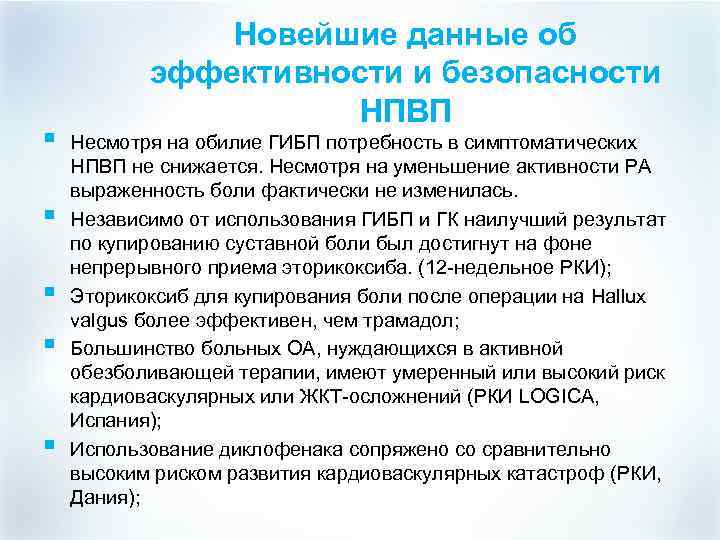

§ § § Новейшие данные об эффективности и безопасности НПВП Несмотря на обилие ГИБП потребность в симптоматических НПВП не снижается. Несмотря на уменьшение активности РА выраженность боли фактически не изменилась. Независимо от использования ГИБП и ГК наилучший результат по купированию суставной боли был достигнут на фоне непрерывного приема эторикоксиба. (12 -недельное РКИ); Эторикоксиб для купирования боли после операции на Hallux valgus более эффективен, чем трамадол; Большинство больных ОА, нуждающихся в активной обезболивающей терапии, имеют умеренный или высокий риск кардиоваскулярных или ЖКТ-осложнений (РКИ LOGICA, Испания); Использование диклофенака сопряжено со сравнительно высоким риском развития кардиоваскулярных катастроф (РКИ, Дания);

§ § § Новейшие данные об эффективности и безопасности НПВП Несмотря на обилие ГИБП потребность в симптоматических НПВП не снижается. Несмотря на уменьшение активности РА выраженность боли фактически не изменилась. Независимо от использования ГИБП и ГК наилучший результат по купированию суставной боли был достигнут на фоне непрерывного приема эторикоксиба. (12 -недельное РКИ); Эторикоксиб для купирования боли после операции на Hallux valgus более эффективен, чем трамадол; Большинство больных ОА, нуждающихся в активной обезболивающей терапии, имеют умеренный или высокий риск кардиоваскулярных или ЖКТ-осложнений (РКИ LOGICA, Испания); Использование диклофенака сопряжено со сравнительно высоким риском развития кардиоваскулярных катастроф (РКИ, Дания);